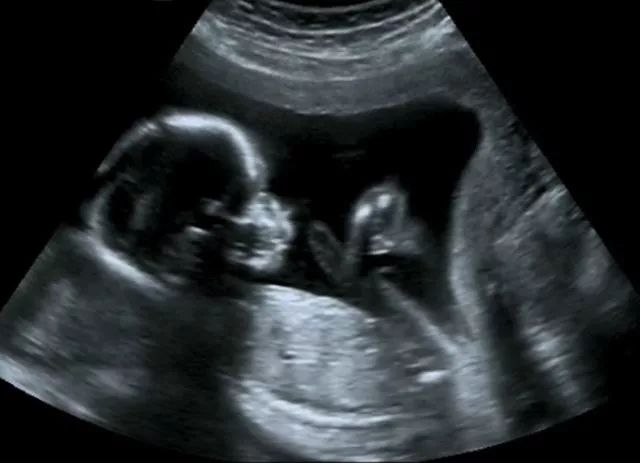

孕4周孕囊太小,做B超还不一定能看到孕囊,一般要等到hcg的值达到1000以上,做阴超才能看到孕囊,hcg的值达到2000以上做腹超才可以看到孕囊,你可以过几天去医院检查一下hcg的值,如果 hcg的值上升到1000或2000以上,就可以做相应的超声检查,看看孕囊是否在子宫腔内,排除宫外孕的可能。